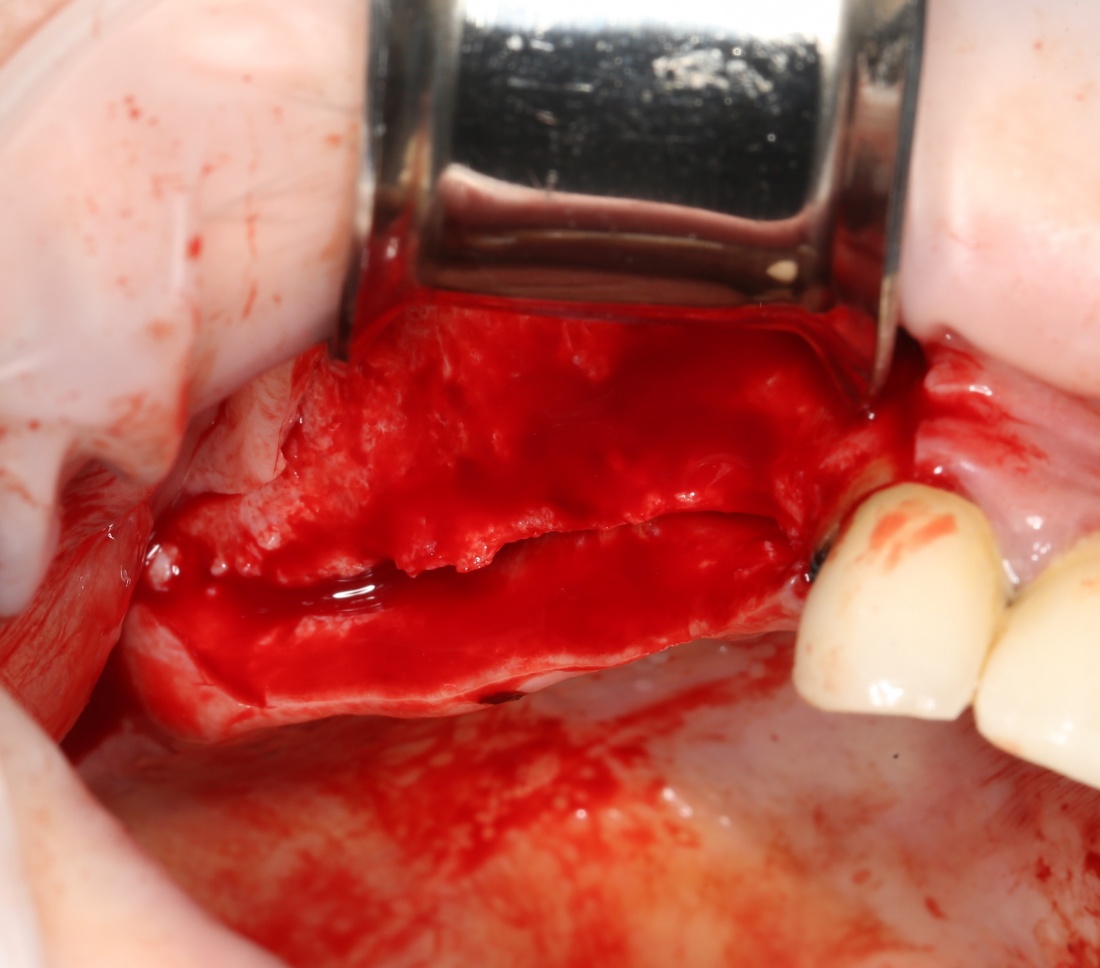

Я же в своей практике для создания доступа использую ультразвук, а именно — электрический пьезохирургический аппарат VarioSurg (NSK). Он позволяет делать очень красивый и практичный доступ любой формы:

- можно сделать доступ любой формы.

- после создания доступа получается костный фрагмент, который мы можем использовать по-разному (для закрытия перфорации, костной пластики,

сварить холодец или чего-нибудь еще)

- можно создавать большие доступы и закрывать их получившимся костный фрагментом, легко обходить септы, шипы и перегородки дна верхнечелюстной полости

- сам процесс создания доступа получается более контролируемым.